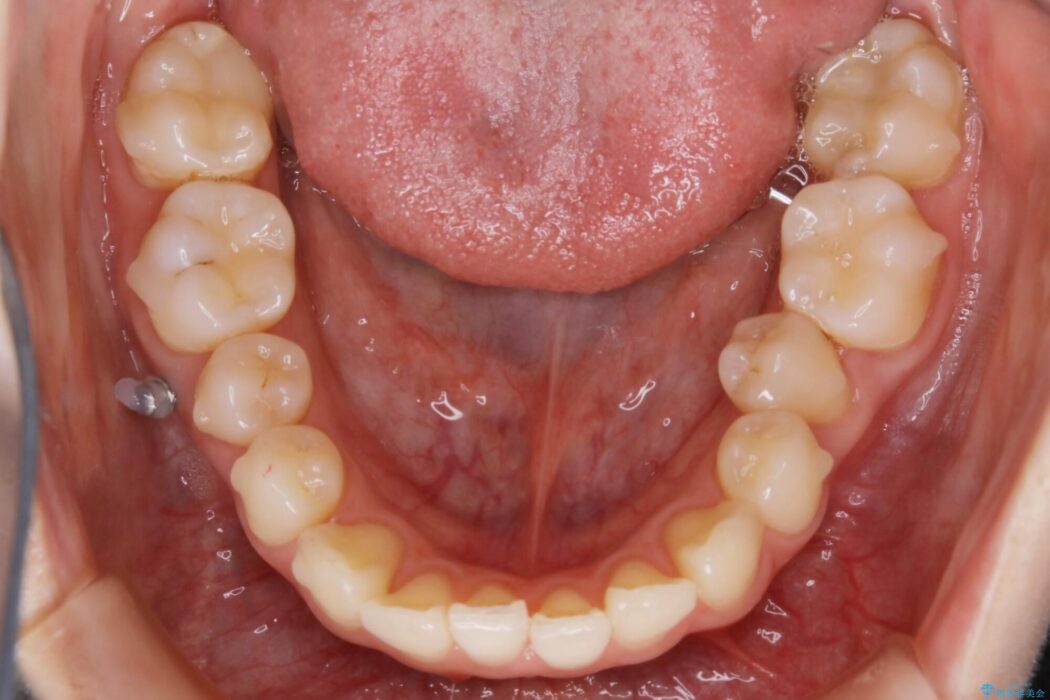

【20代女性】ブライダルに向けた矯正できれいなスマイルラインへ

ガタつきの度合いから抜歯は不要と判断しましたので、マイクロインプラントを用いて歯全体を遠心移動させていくことでねじれや噛み合わせのズレを改善していく計画を立てました。